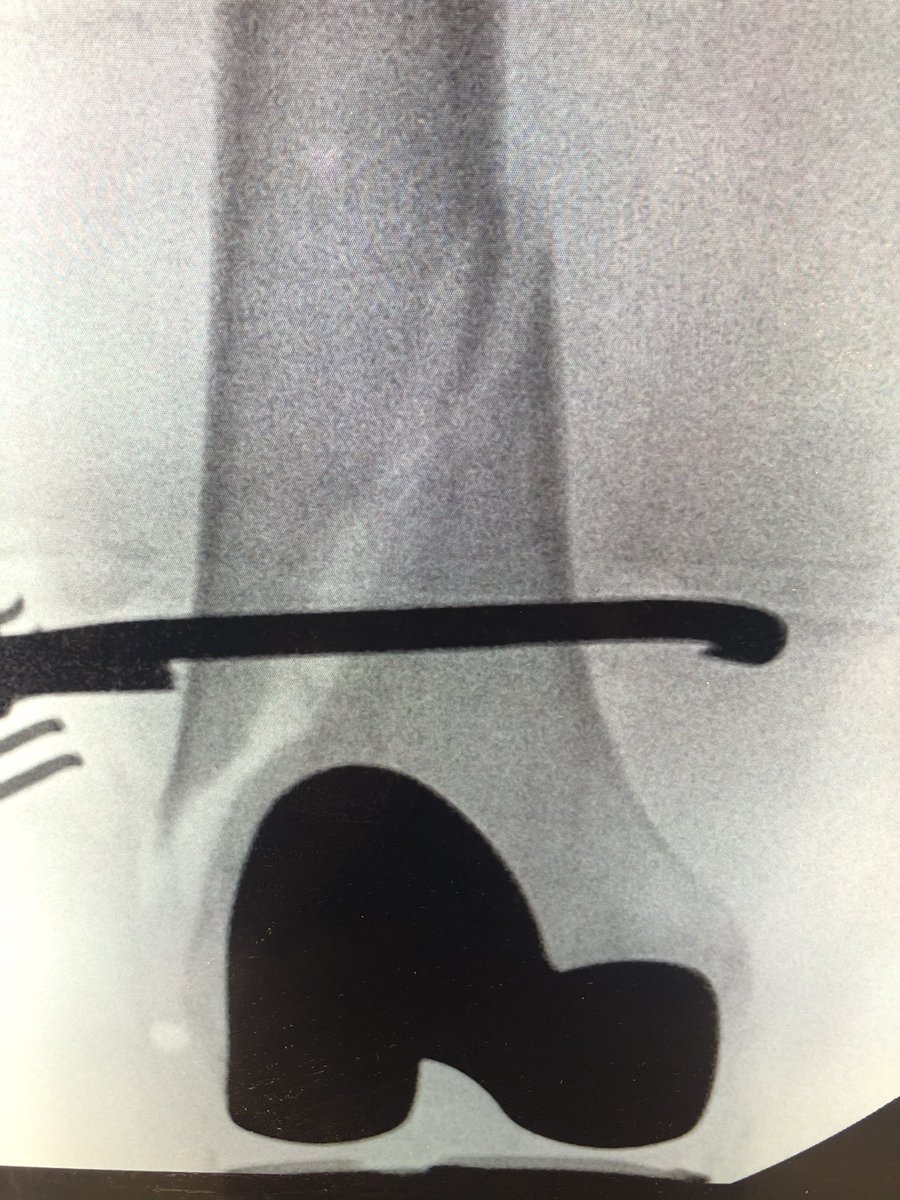

[4/5] Clamp then stayed on the entire time and retrograde nail went in. Here I am forced into posterior starting point which I knew would give me a slight malreduction problem in the end; I aimed to minimize that by keeping the clamp on until nail was locked proximal and distal.

[5/5] Finals. Looks great on AP, but on lateral we still ended up with a little malreduction because starting point limited. But bone was good and 3 screws in distally, so I was not concerned. If you want a paper about which knees have a posterior start: https://pubmed.ncbi.nlm.nih.gov/24929282/